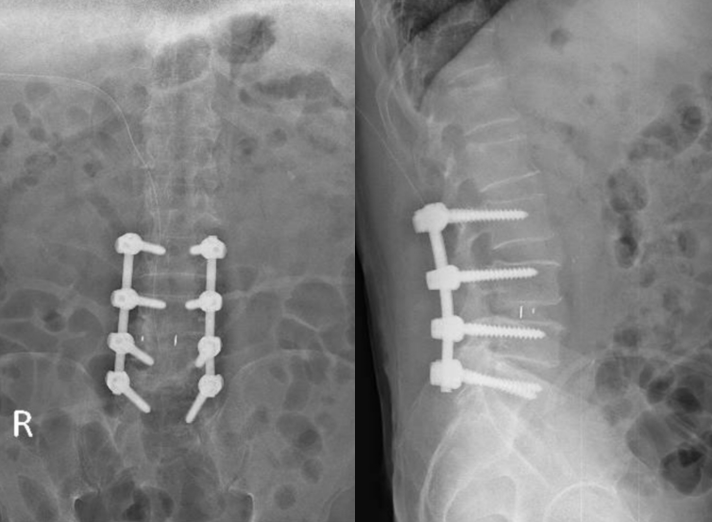

- Phẫu thuật được chỉ định khi bệnh nhân điều trị nội khoa, phục hồi chức năng không đáp ứng hoặc bệnh nhân có biểu hiện của hội chứng tổn thương chùm đuôi ngựa.

Phẫu thuật thuật thoát vị đĩa đệm - hẹp ống sống lưng hiện được thực hiện thường quy tại Bệnh viện đa khoa tỉnh Quảng Trị:

2. Hình ảnh: Internet, khoa Chẩn đoán hình ảnh BV Đa khoa Tỉnh Quảng Trị